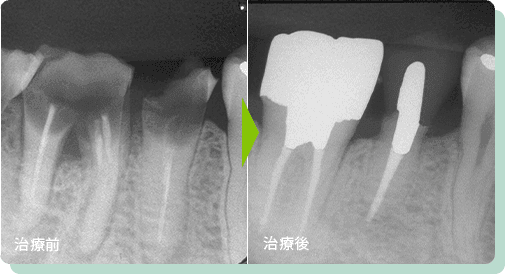

移植した例

親知らずを欠損部へ移植

患者さまのお口の使っていない親知らずを、すぐ前の欠損部へ移植しました。術後3年半、問題なく経過しています。

こういった歯の活用を行い、しっかりとご自身の歯で噛めることを考えると、親知らずだからと言って全て抜歯してしまうだけが選択肢ではないと考えられます。

リスク:疼痛・出血・抜歯時に伴う痛みなど

費用:保険適応(症状やケースに応じて適応となります)